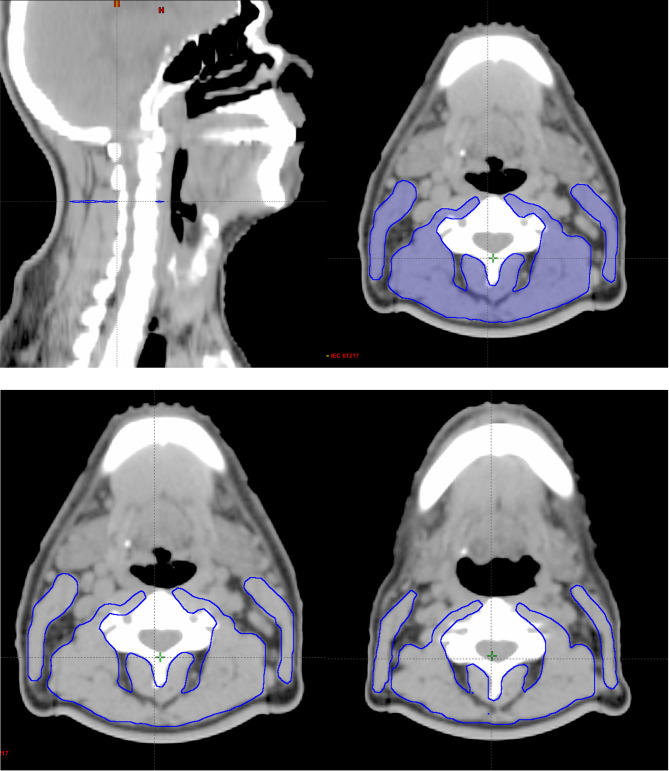

Methods: For this study, we analyzed 30 patients who received radiotherapy in our clinic between September 2018 and September 2021. Those patients, both regular and completed weekly dietitian counseling notes during radiotherapy and available adaptive radiotherapy planning images, were included in the analysis. All patients had weekly nutritional interventions, including nutritional and anthropometric changes in weight, height, body mass index (BMI), and lean body mass (LBM). Skeletal muscle volume, called cervical muscle gauge (CMG), was measured from the simulation images of beginning and adaptive radiotherapy. Inflammatory parameters, including the neutrophil-lymphocyte ratio (NLR), the platelet-lymphocyte ratio (PLR), and the systemic inflammatory index (SII), were also calculated from weekly total blood counts. For the analysis, anthropometric measurements were compared at the beginning and adaptive treatment time. Progression-free (PFS) and overall (OS) survival were calculated according to weight and CMG changes.

Conclusions: Cervical muscle volume measurement may help predict malnutrition in patients receiving radiotherapy for head and neck cancer. Our study shows adaptive planning images may be used for this approach. In addition, this method may help to predict prognosis due to malnutrition in patients undergoing radiotherapy.